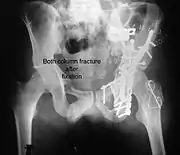

Both column fracture after fixation with screws and plates